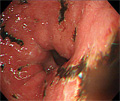

- ★(4)Gastritis (acute gastritis)

Gross appearance: Endoscopic view of AGML (acute gastric mucosal lesion). There is erosive gastritis demonstrated by multiple erosive, hemorrhagic foci in the gastric pylorus (arrow).

Click the image to see the enlarged image.